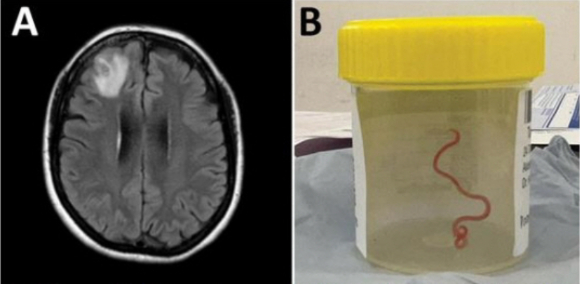

호주 뉴사우스웨일스 출신의 이 여성은 지난 2021년 1월 복통, 설사, 발열 등 증상을 호소하다 지역병원에 입원했다. 이듬해 여성은 건망증과 우울증 증세도 보이기 시작했고, 캔버라 병원에서 자기공명영상장치(MRI) 검사를 진행한 결과, 수술이 필요하다는 소견이 나왔다.

이후 수술을 집도하던 신경외과의 하리 프리야 반디 의사는 수술 도중 충격적인 장면을 목격했다. 환자의 뇌에서 8㎝ 길이의 기생충을 발견했기 때문이다. 또 그 기생충은 뇌에서 나와서도 살아서 꿈틀대고 있었다.

호주 연방과학산업연구기구(CSIRO)는 이 기생충을 '오피다스카리스 로베르시'라는 회충으로 확인했다고 밝혔다. 이 회충은 주로 비단뱀 체내에서 발견되며, 사람 몸에서 발견된 건 이번이 처음이다.